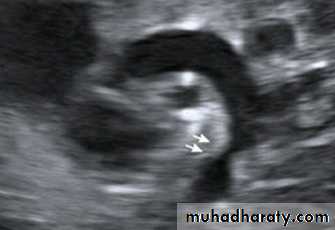

Antenatal diagnosis

Fetal anomaly scan is performed between 18 and 20 weeks' gestation. If an abnormality is detected, detailed fetal echocardiography is performed by a paediatric cardiologist, who also checks any fetus at increased risk, e.g. where Down's syndrome is suspected, where the parents have had a previous child with heart disease or where the mother has C.H.D. The continuation of pregnancy and delivery then planned.